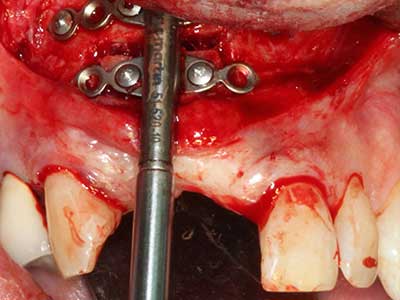

Fig. 3: Basal separation of the block is easier with specially angled attachments.

Fig. 4: Additional autologous bone chips are harvested with the bone scaler.

Fig. 5: Checking the block size at the recipient site.